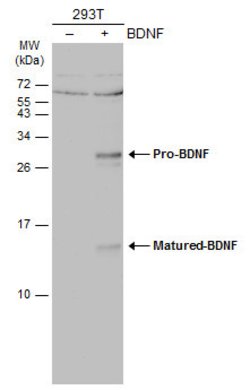

Keep as concentrated solution. Predicted reactivity: Mouse (100%), Rat (100%), Dog (100%), Cat (100%), Pig (100%), Chimpanzee (100%), Bovine (100%). Positive Control: mouse brain, rat brain, BDNF-transfected 293T. Store product as a concentrated solution. Centrifuge briefly prior to opening the vial.

BDNF (Brain-Derived Neurotrophic Factor) is a member of the neurotrophin family. BDNF is synthesized as pre-proBDNF, followed by cleavage to proBDNF. Although further processing generates the mature, 14 kDa protein, pro-BDNF is biologically active and is secreted in synaptic vesicles along with the mature form. BDNF is widely expressed in the central nervous system and acts in an autocrine and paracrine manner on several classes of neurons. Signaling occurs mainly through the tyrosine kinase receptor TrkB, although binding to the lower-affinity receptor, p75-NTR, has also been demonstrated. BDNF promotes neuronal survival and differentiation and has been shown to play a critical role in memory formation and synaptic regulation. BDNF is induced by cortical neurons, and is necessary for survival of striatal neurons in the brain. Expression of BDNF is reduced in both Alzheimer's and Huntington disease patients, and may also play a role in the regulation of stress response and in the biology of mood disorders.